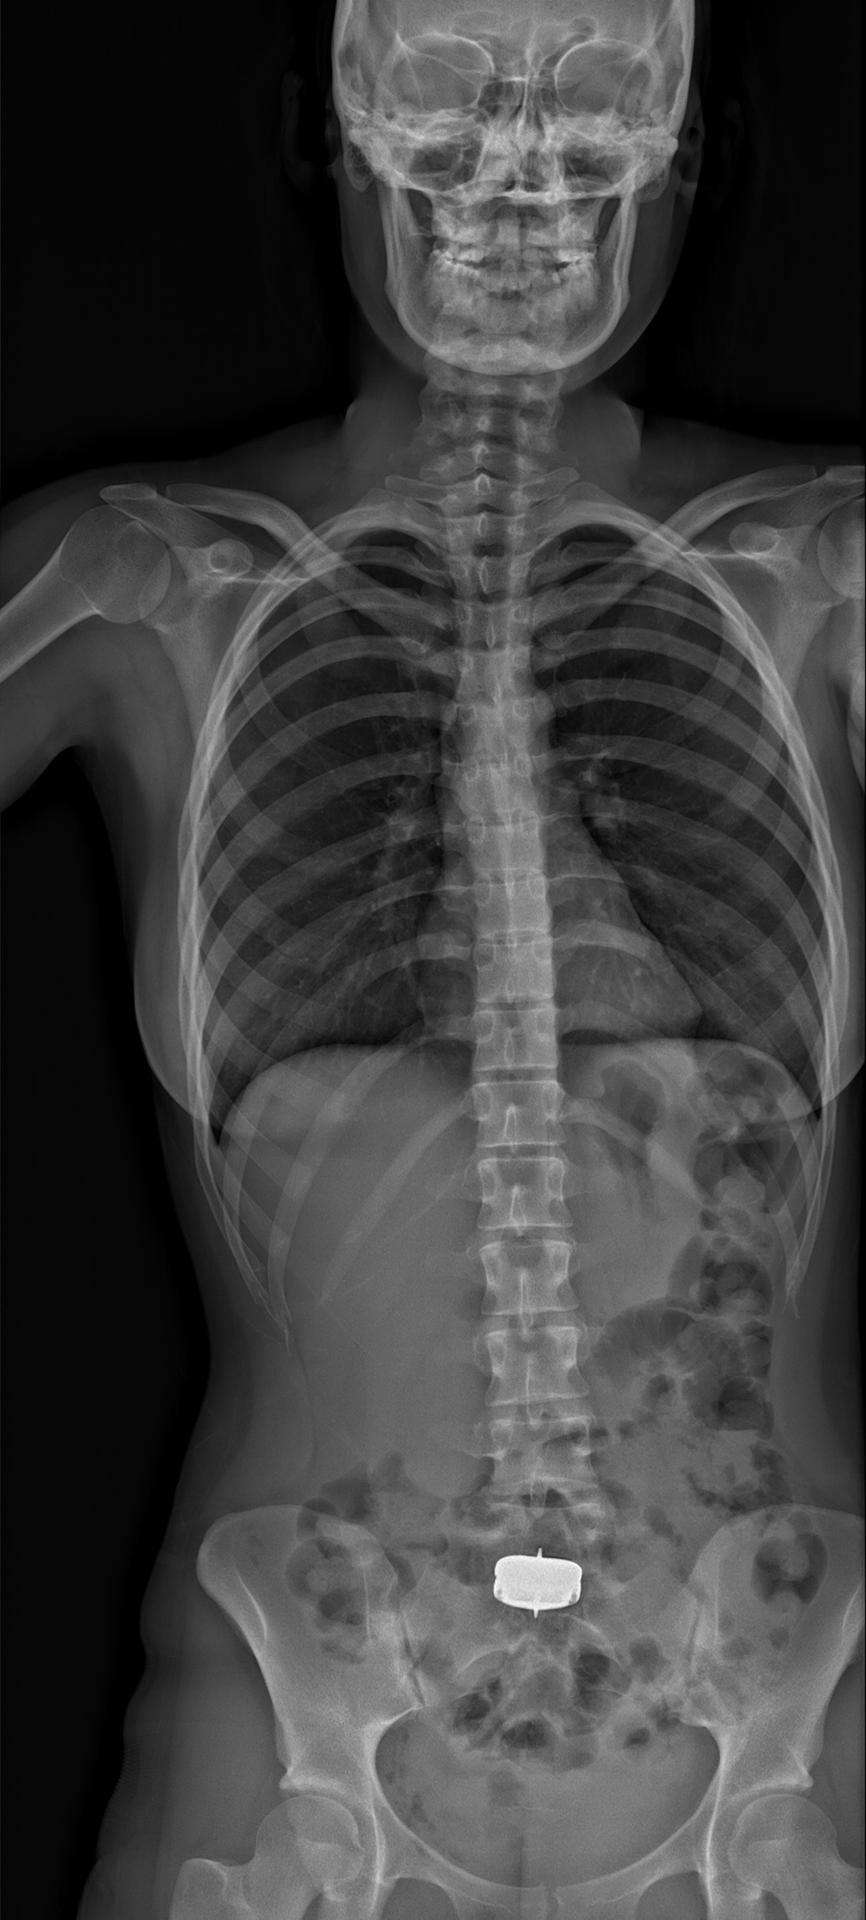

Рентгеновский эффект создает фантастические композиции в этих фотографиях девушки, чье тело становится прозрачным, демонстрируя скелет и внутренние органы. Она позирует в разных позах, ее силуэт светится загадочным свечением. Каждый кадр передает атмосферу научной фантастики и медицинского искусства. Ее кожа кажется полупрозрачной, позволяя увидеть кости и мышцы. Фотографии рассказывают о хрупкости человеческого тела и его внутренней красоте. Девушка то стоит в задумчивости, то делает грациозное движение. Эти иллюстрации вдохновляют на размышления о человеческой анатомии и уязвимости. Каждая картинка - это момент прозрения, когда внешнее уступает место внутреннему. Девушка воплощает образ современной Медузы, сочетающей красоту и загадочность.